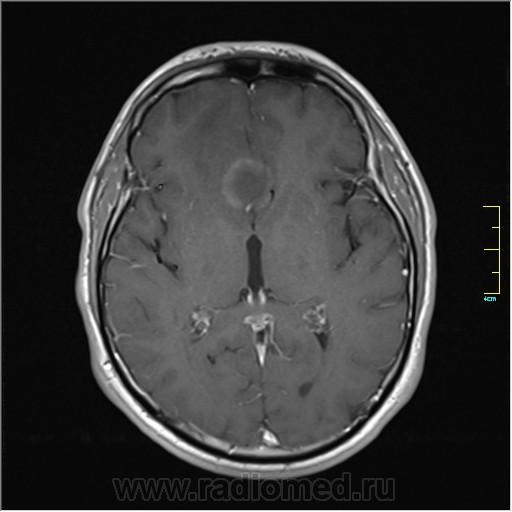

Пациентка направлена на исследование с диагнозом "Гипертонический криз", энцефалопатия неуточненная.

Post-GAD:

частично функционирующая аневризма

Иначе говоря, аневризма с хронической геморрагией, т.к. мы видим фракции крови различного возраста.

Пожалуйста!

Кстати, я этот случай выложил не только чтобы показать, но и чтобы посоветоваться. Мне именно такая картинка впервые попалась, и может быть я в чем-то не прав. Буду рад услышать ваше мнение.

По-моему, аневризма с пристеночными тромбами.

Постепенное пристеночное образование тромбов приводит к появлению типичного для аневризмы феномена -слоистости МР сигнала в полости аневризмы. Данная картина демонстрирует слоистый характер тромботических масс в полости аневризмы .Функционрирующая часть имеет низкий сигнал во всех режимах сканирования. Дополнительно-перифокальный отек.

А может более корректно интерпретировать как частично тромбированная аневризма... Уж коь речь идет о фракциях, ну то есть о тромбе по сути.... Ну и плюс перфокальный отек головного мозга (вероятнее цитотоксический+вазогенный).